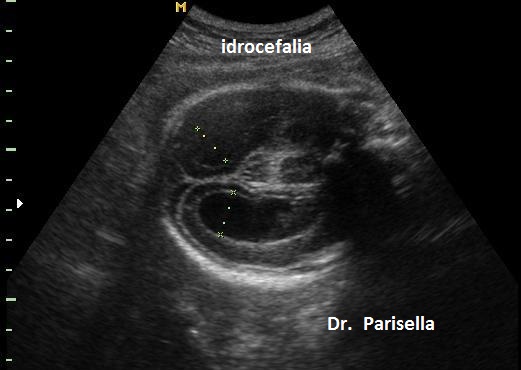

Idrocefalo X-Linked da Stenosi dell'Acquedotto di Silvio (HSAS) OMIM 307000

E' la più comune forma di idrocefalo ereditario, legato a mutazioni del gene L1CAM che mappa in Xq28. Caratteristicamente presenta idrocefalia e pollici addotti. L'idrocefalia è legata a stenosi dell'acquedotto di Silvio ed è quindi di tipo triventricolare con interessamento dei ventricoli laterali e del terzo ventricolo. Possono essere presenti altre anomalie del SNC come l'ipoplasia del corpo calloso.